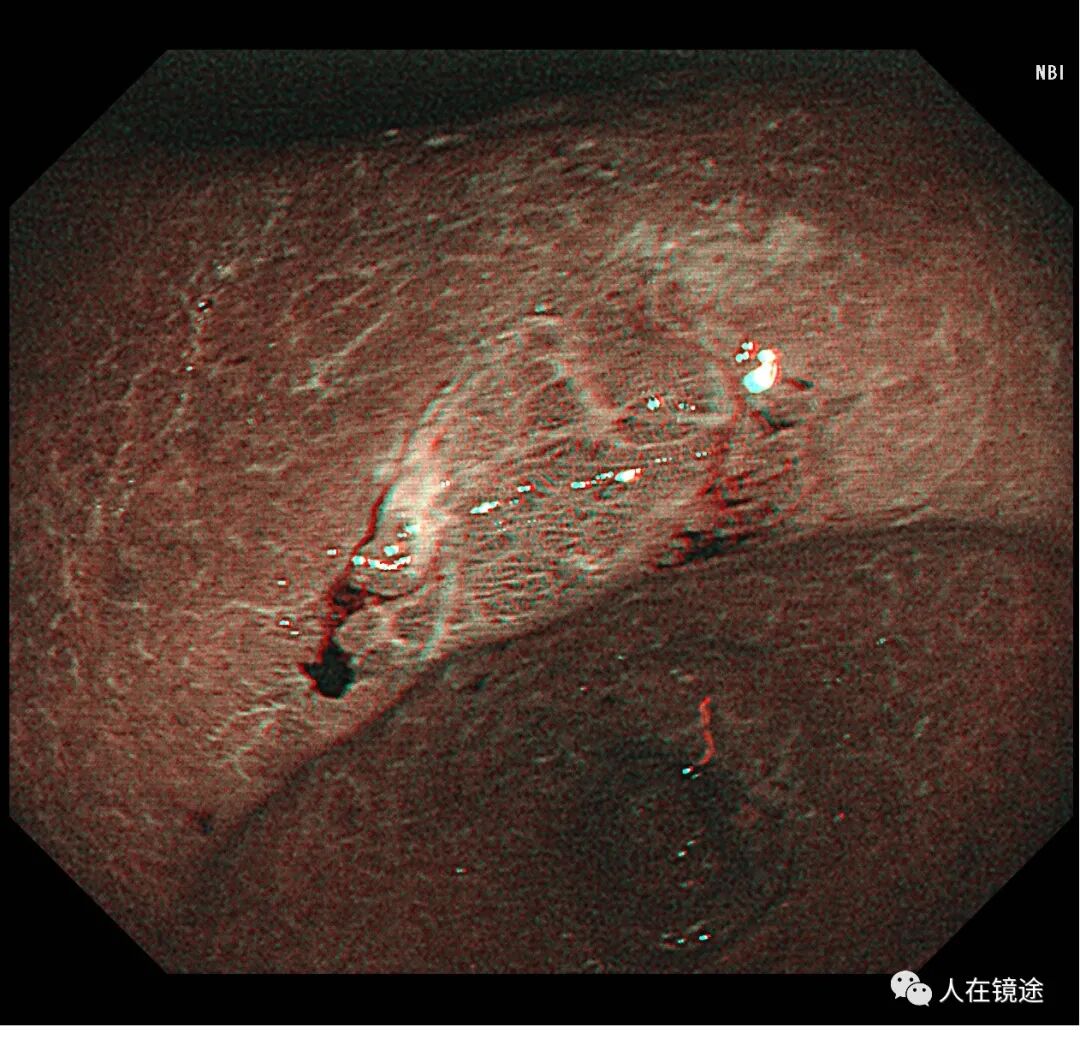

NBI+近焦示:胃窦小弯见一0.8*1.2cmIIa粘膜发病变呈咖色,边界清楚,微结构紊乱,表面粘膜高低不平伴自发性出血

靛胭脂染色示:病变边界清楚,约0.8*1.2cm大小,表面粘膜高低不平,微结构紊乱伴自发性出血。

NBI+靛胭脂+近焦示:病变边界清楚,约0.8*1.2cm大小,表面粘膜高低不平,微结构紊乱伴自发性出血